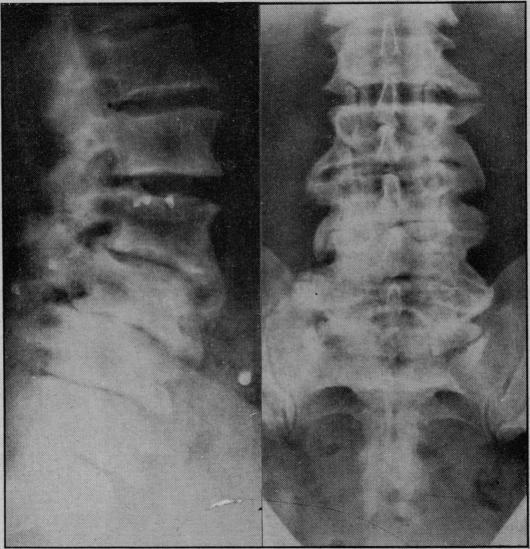

Tabetic spinal arthropathy.

Proc R Soc Med. 1953 Sep;46(9):747-52. doi: 10.1177/003591575304600908.